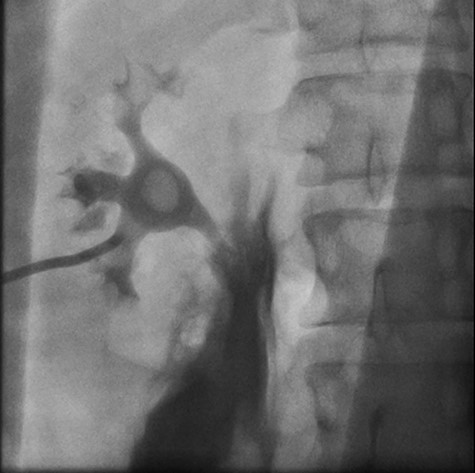

Right retrograde cystoscopy exhibiting extravasation of contrast.

Left retrograde cystoscopy exhibiting extravasation of contrast.

Cystoscopy with retrograde pyelogram was performed by the urology team and this showed total disruption of the UPJ bilaterally with extravasation of contrast (Figs 3 and 4). She underwent bilateral interventional radiology nephrostomy tube placement. The definitive repair was planned for after pregnancy, but she required tube changes every 6 weeks. There was no fetal distress during her stay. She recovered well and was discharged after 5 days.